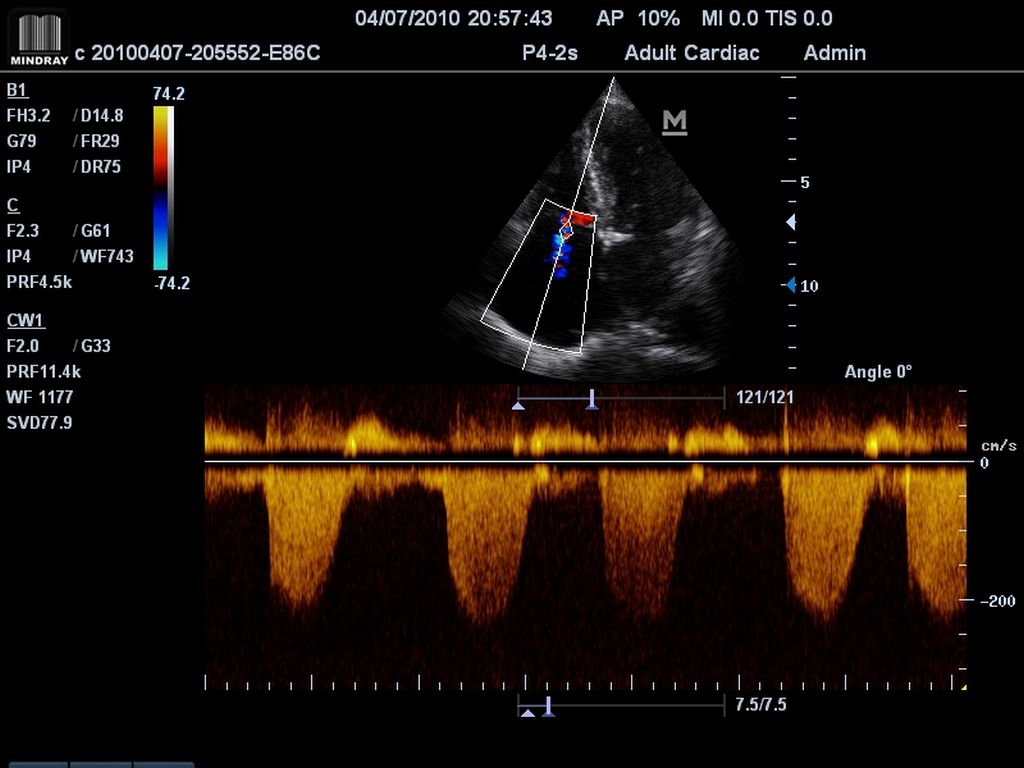

Klinické obrázky:

- triplexný mód a automatické pomeranie celého spektra Pulzného Dopplera

- Pulzný, Spektrálny Doppler (PW), citlivý Farebný Doppler (CFM), ultracitlivý smerový Power Doppler (PDI), anatomický - M mód a Stress Echo

- Smart PW/CW